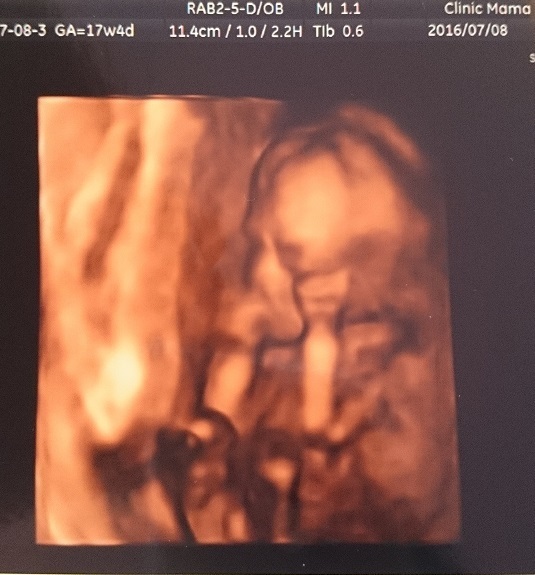

17週6日(17w6d・男の子)|よぴ1126 さん(28歳)

エコー写真撮影時のエピソード:

初めて4Dエコーをした時で、2Dの時とは違って、赤ちゃんの姿がはっきり見えることに感動したのを覚えています。お顔や姿がとてもかわいかったです。その思い出のエコー写真と一緒に妊娠期の思い出を残したくて、妊娠29週の時にマタニティフォトを撮りました。